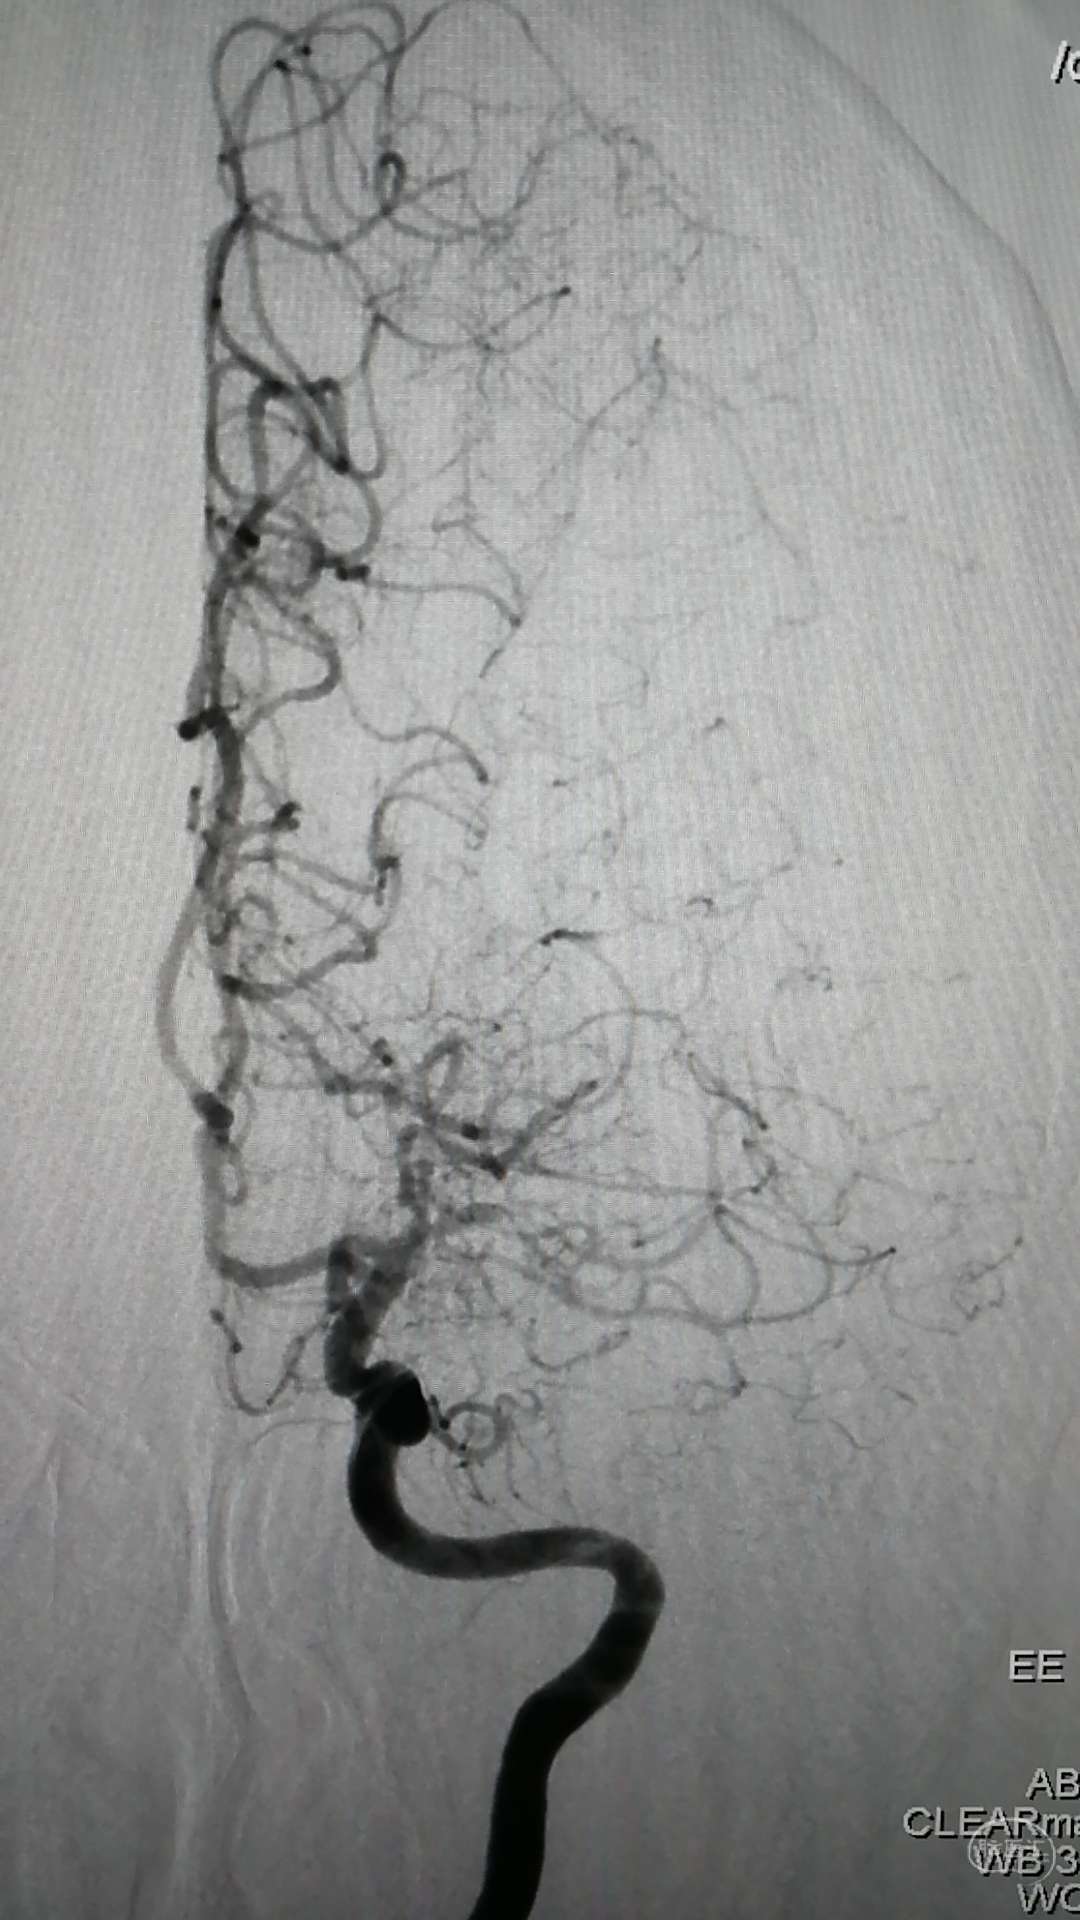

DSA示:左侧大脑中动脉闭塞,烟雾样血管形成。

DSA示颞浅A未向颅内代偿。

DSA示:左侧大脑前、大脑中动脉闭塞,烟雾样血管形成。